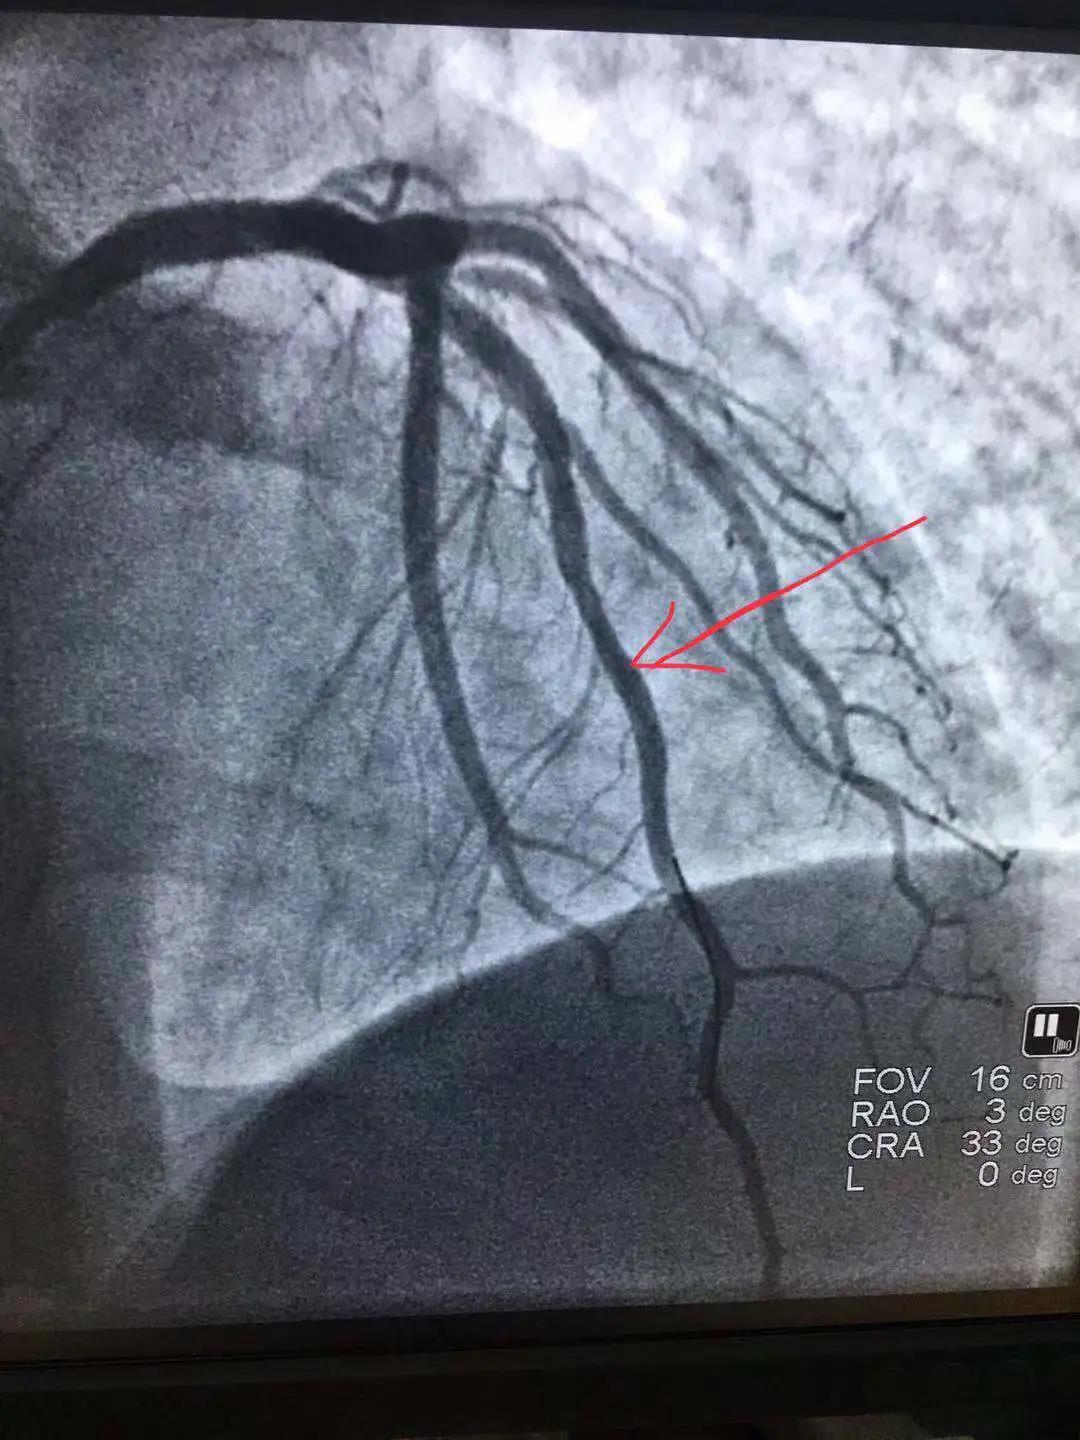

心內(nèi)科醫(yī)務(wù)人員冠狀動脈造影中

“冠狀動脈造影”即“冠脈造影”,是診斷冠心病的一種常用方法,作為一種有創(chuàng)診斷技術(shù),它被稱為診斷冠心病的“金標(biāo)準(zhǔn)”。心內(nèi)科融無創(chuàng)與有創(chuàng)協(xié)同治療為一體,硬件設(shè)施齊全,配有美國GE大C型臂數(shù)字減影X線造影機(jī),心臟臨時(shí)起搏器、床旁監(jiān)護(hù)儀、除顫儀、自動分析心電圖等,設(shè)有心臟重癥監(jiān)護(hù)室(CCU),擁有1個(gè)獨(dú)立導(dǎo)管室,設(shè)有心內(nèi)科??崎T診、心內(nèi)科病房(現(xiàn)有床位71張)、心血管無創(chuàng)檢查室、心電圖室等部門。科室現(xiàn)已熟練開展冠狀動脈造影技術(shù),為心血管疾病患者帶來了福音。